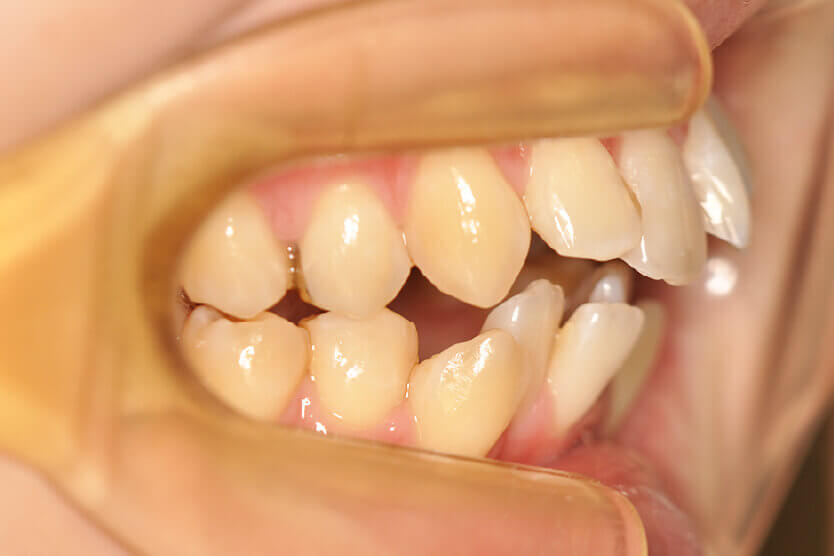

開咬(抜歯)【1979】

初診時

年齢

21歳 性 別 女性

治療内容の詳細 初診時21歳の女性で、出っ歯、下顎前歯部のがたつきを気にされ来院されました。

検査の結果、上顎前突、上下顎前歯部叢生および開咬を伴うアングルⅡ級1類不正咬合と診断しました。

治療としては、上下左右第一小臼歯を抜歯して、セルフライゲーションブラケット装置(デーモンシステム)とマウスピース型矯正装置(インビザライン)で配列を行いました。

この際、上顎に歯科矯正用アンカースクリューを設置し上顎前歯部後退時の土台としました。

開咬については、顎間ゴムの協力もあり改善されました。